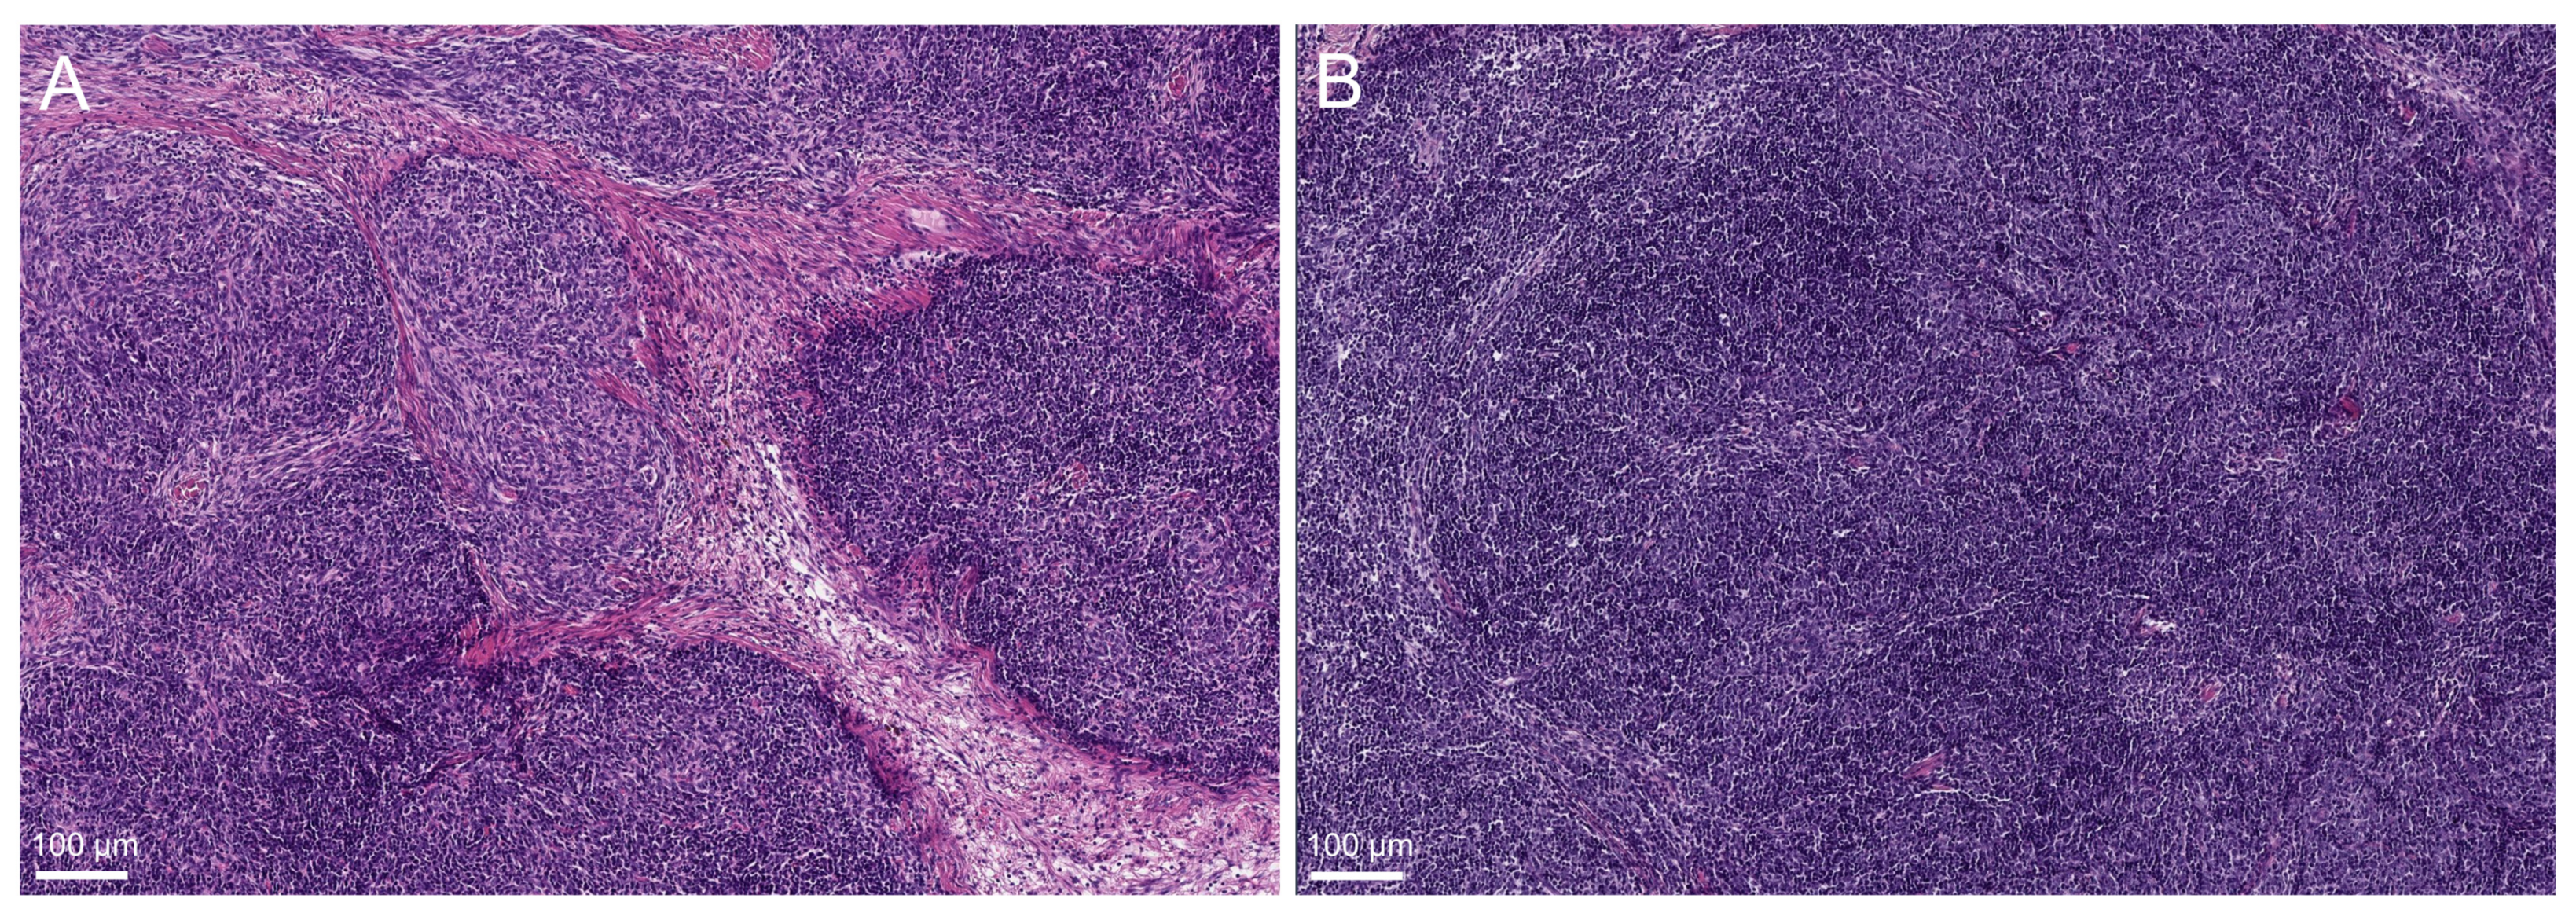

3.1. Thymoma Methylation Classes and Histological Characteristics

4.2. (b) Methylation Analyses Separate AB-Thymomas into Two Subgroups: Monophasic and Bi-Phasic AB-Thymoma

4.3. (c) Methylation Analyses Separate B2-Thymomas into Two Subgroups: Conventional and “B1-like” B2-Thymomas